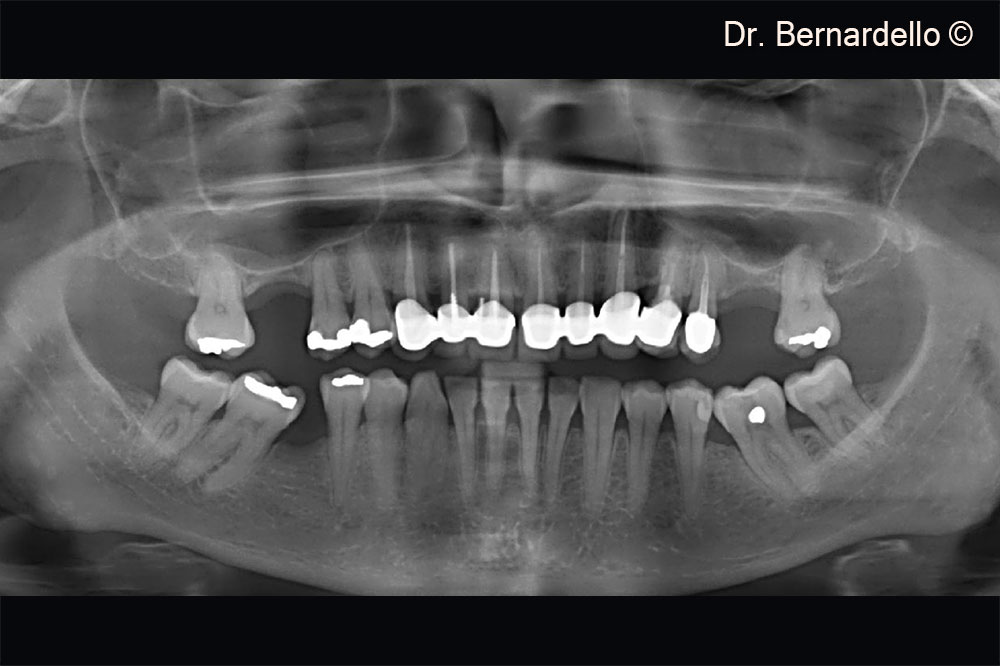

Transcrestal sinus floor elevation with the hydrodnamic technique

Dr. Fabio Bernardello